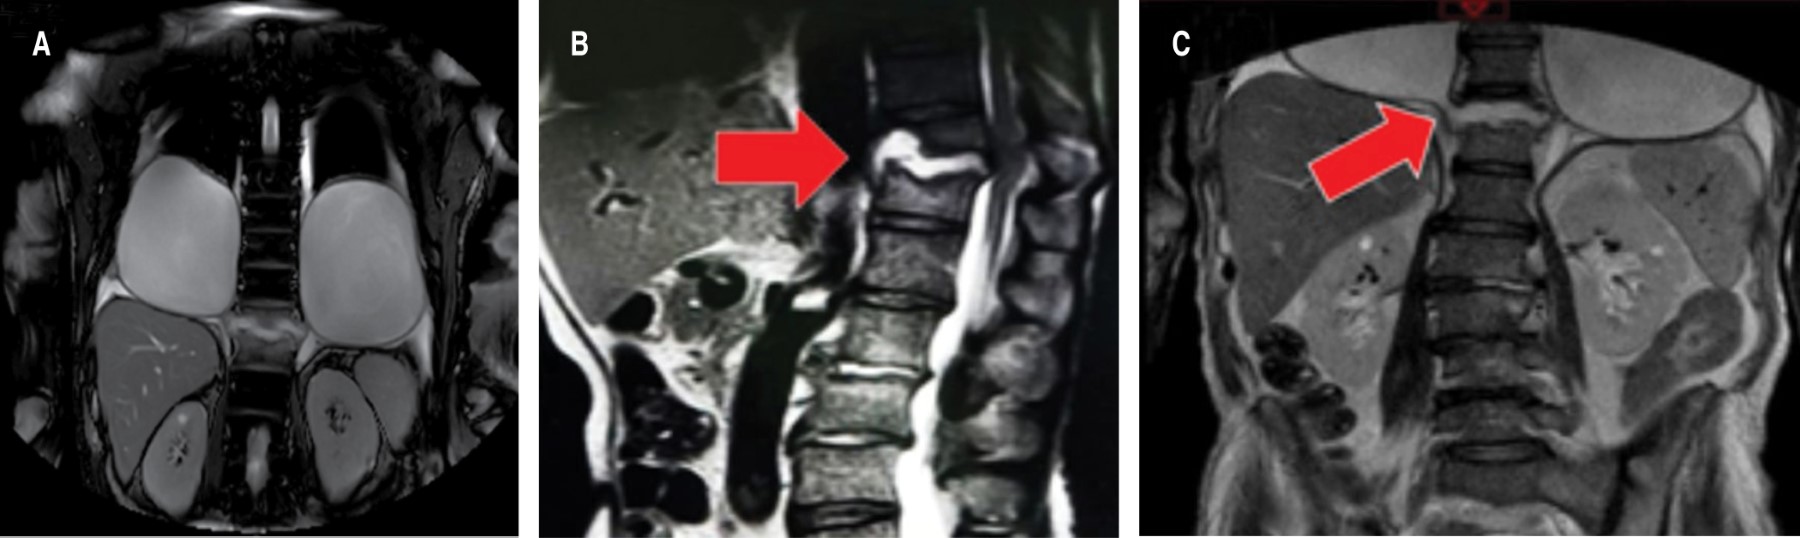

Magnetic resonance imaging (MRI) was performed, which documented, in pleural space, oval images of hypointense interior in T1, hyperintense T2 and SPAIR with wall thickening up to 11 mm, presented communication with destroyed vertebral body in T12, which presented changes due to spondylodiscitis that conditioned spinal cord contact and increase in its amplitude without change in intensity (Figure 2).